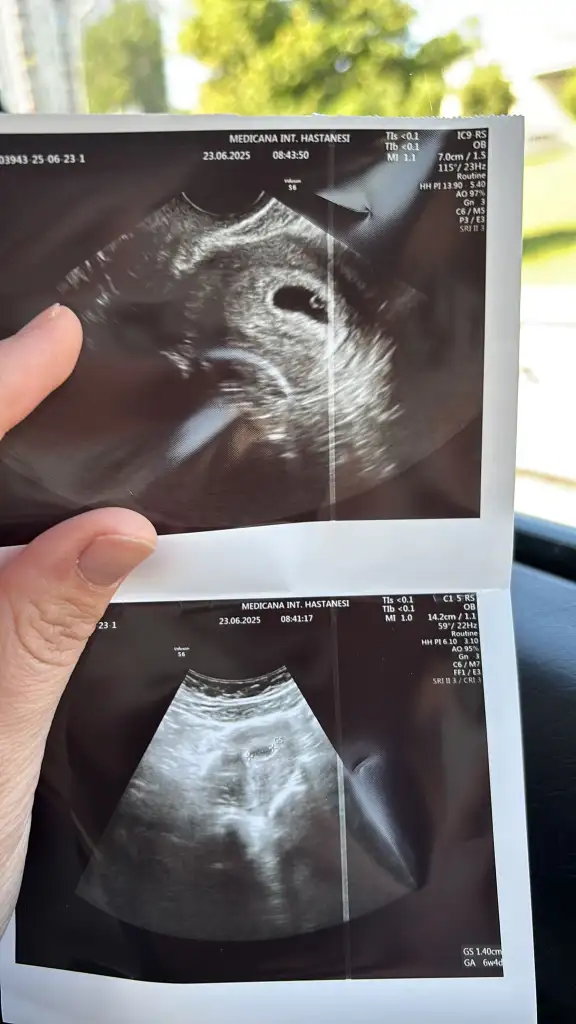

Erkeğe benziyor canımbenim için de bakar mısınız ilki 6 +4 ikinci fotoğraf 8+3 sonuncusu 10+1 Eki Görüntüle 3623528 Eki Görüntüle 3623526 Eki Görüntüle 3623525